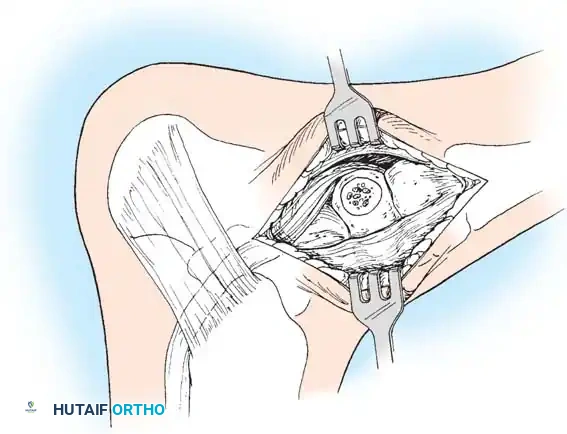

🔪 Surgical Technique 79-6: The Kidner Procedure

1. Incision and Exposure

-

Incision: Begin the skin incision 1 to 1.5 cm inferior and distal to the tip of the medial malleolus. Arch the incision slightly dorsalward, peaking directly over the medial prominence of the accessory navicular, and slope it distally to the base of the first metatarsal.

-

Dissection: Carefully dissect through the subcutaneous tissues. Identify and ligate the plantar communicating branches of the saphenous venous system. Protect the terminal branches of the saphenous nerve.

-

Tendon Identification: Identify the posterior tibial tendon as it approaches the accessory navicular.

-

Tendon Exposure: Identify the dorsal and plantar margins of the PTT approximately 2 cm proximal to the accessory navicular. Expose the tendon distally, ending at the bone.

Surgical Warning: It is imperative to expose the entire tendon without disturbing the portion extending plantarward toward its multiple insertions on the cuneiforms and metatarsal bases. Preserving these plantar slips maintains the structural integrity of the midfoot.

2. Transposition and Advancement of the PTT

-

Ossicle Excision: Using sharp dissection, meticulously shell the accessory navicular out from the substance of the posterior tibial tendon. If transposition of the tendon is planned, attempt to leave a microscopic sliver of bone within the tendon to enhance subsequent bone-to-tendon healing.

-

Navicular Resection: Resect the medial prominence of the main navicular so that it is flush with the medial border of the first cuneiform. This is typically achieved using an osteotome, followed by a rongeur and rasp to smooth the cortical edges.

-

Tendon Advancement: Suture the PTT to the apex of the medial longitudinal arch. This can be achieved by utilizing local periosteum and ligamentous tissue to secure the transposed tendon slip, or by passing heavy non-absorbable sutures through drill holes placed in the center of the navicular and tying them dorsally.

- Biomechanical Reduction: Try to advance this slip of tendon while the talonavicular joint is anatomically reduced. Reestablish the medial longitudinal arch by holding the midfoot and forefoot in a cavovarus position during knot tying.